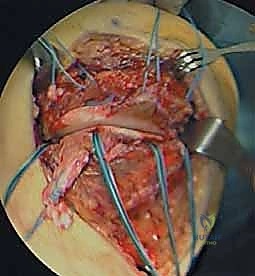

يُستخدم هذا الإجراء عادةً للإصابات الحادة (التي لم يمر عليها أكثر من 3 أسابيع)، وتحديداً عندما يتمزق الرباط من نقطة اتصاله بعظمة الفخذ أو قصبة الساق.

- الخطوة الأولى (التخدير والتحضير): يتم تخدير المريض (نصفياً أو كلياً). يتم إجراء فحص بالمنظار (Arthroscopy) أولاً للتأكد من عدم وجود إصابات داخلية في الغضاريف أو الأربطة الصليبية ومعالجتها إن وجدت.

- الخطوة الثانية (الوصول للرباط): يتم عمل شق جراحي صغير ودقيق على الجانب الداخلي للركبة للوصول إلى الرباط الممزق.

- الخطوة الثالثة (التثبيت): يستخدم الدكتور هطيف تقنيات متطورة مثل "الخطاطيف العظمية" (Suture Anchors) وهي براغي صغيرة جداً تُزرع في العظم ويخرج منها خيوط طبية فائقة القوة. يتم خياطة الأطراف الممزقة من الرباط وربطها بإحكام إلى هذه الخطاطيف لإعادة تثبيت الرباط في مكانه التشريحي الأصلي.